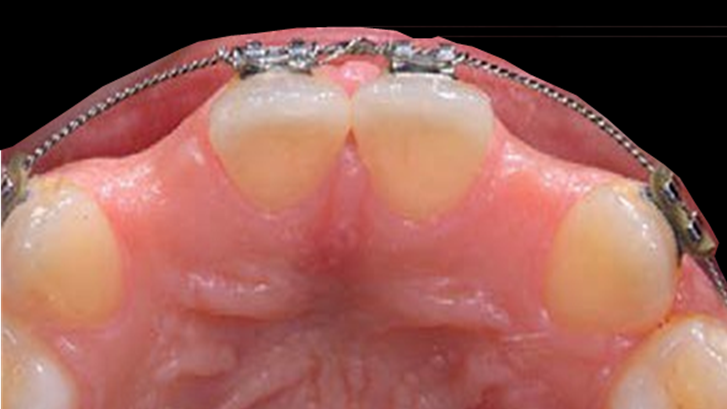

Clinical case: Patient-centered approach: treatment strategy for Root Membrane Technique & delayed implant placement

- Courtesy of Dr. Yoshiharu Hayashi, Japan -

Socket Shield Technique, anterior esthetics, maxillary anterior, esthetic, esthetics, delayed implant placement, socket preservation, AnyRidge, Root Membrane Kit, Root Membrane Technique, Partial Extraction Therapy, PET, esthetic zone, fuse abutment, Dr. Yoshiharu Hayashi,#11,#21,#22

Products:

AnyRidge implant system, fuse abutment Root membrane kit, PET Kit